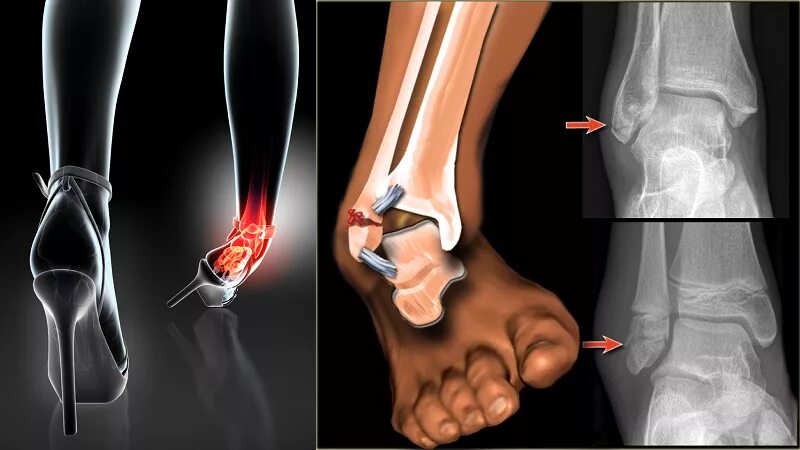

Перелом костей голени код по мкб 10